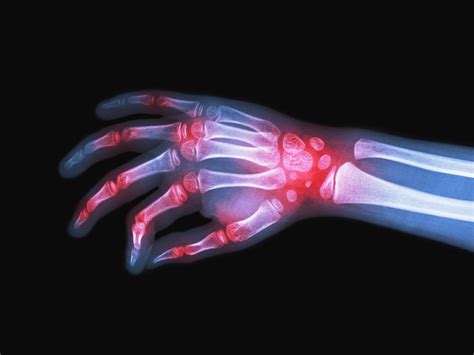

Sintomas da artrite nas mãos - Artrite Reumatóide

A AR caracteriza-se tipicamente por inflamação sinovial persistente, resultando em dor, edema, calor e rigidez articular. Atinge, com frequência, pequenas articulações das mãos e pés de forma simétrica. Além das manifestações articulares, a AR pode apresentar sintomas extra-articulares, como nódulos reumatoides, vasculite, manifestações pulmonares, cardíacas e oculares. O diagnóstico baseia-se na avaliação clínica, exames laboratoriais (fator reumatoide, anti-CCP, VHS, PCR) e exames de imagem (radiografias, ultrassonografia, ressonância magnética), conforme estabelecido pelos critérios de classificação ACR/EULAR 2010.